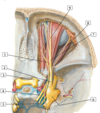

1 - stylohyoid muscle

1 - Digastric muscle

1 - trochlear nerve (IV)

2 - ophthalmic nerve (V1)

3 - optic nerve (ii)

4 - oculomotor nerve (iii)

5 - abducent nerve (VI)

6 - trigeminal (semilunar) ganglion

7 - frontal nerve

8 - lacrimal nerve

9 - supra-orbital nerve